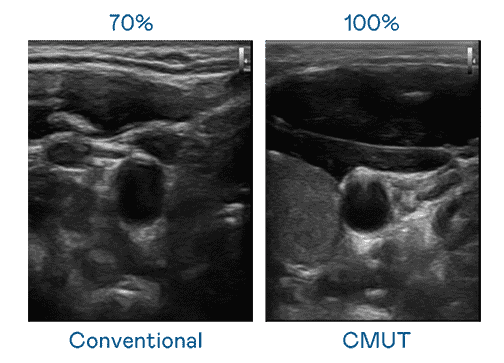

CMUT 技术是一种用电容式微机电元件来产生超音波讯号的技术。。。与传统 PZT 压电式技术相比,,,CMUT 频宽增加 30%,,,更宽频的超音波讯号让影像解析度大幅提升,,,是实现高影像品质医疗超音波扫描、、促进精准医疗发展的关键技术。。。。

超音波影像的解析度高低,,首先取决于探头能发出的讯号频宽。。万利 CMUT 可提供高清晰的超音波讯号,,,,提供高频宽、、、高灵敏度、、、、影像纹理细节更高的超音波影像,,协助医护人员缩短影像判读时间及利用精准的医疗影像进行诊断。。